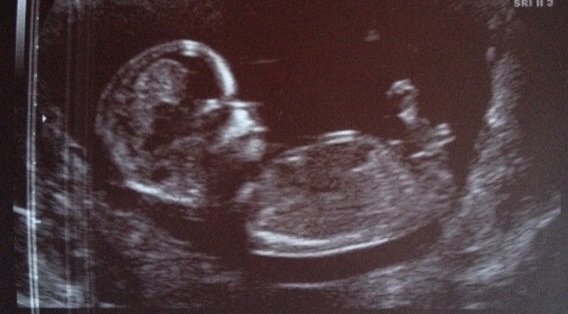

Girl Sent from my iPad using Tapatalk

Girl :)

I'm guessing girl. Do you want to have a guess on mine?

Maybe girl xx